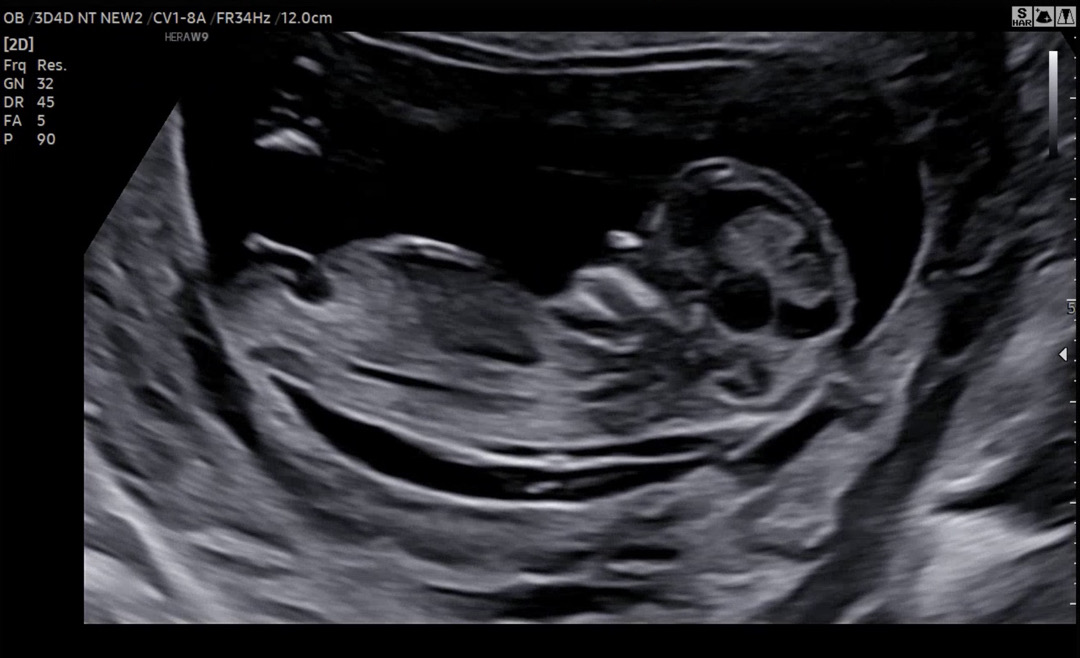

12주0일 각도법 마미들 부탁드려요!

안녕하세요! 12주 0일인데,, 각도법 궁금해서 의견 부탁드립니다!! 감사합니다❤️

돌기가 안 보이는 사진이예요